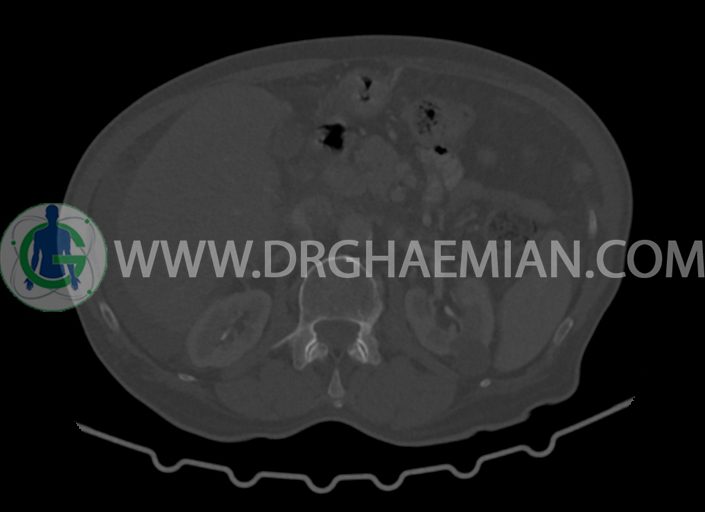

در سی تی اسکن اسپیرال شکم و لگن با کنتراست خوراکی و وریدی (مولتی دیدکتور 16 با مقاطع ظریف و بازسازی های ساژیتال و کرونال) :

–پروستات با دیامتر عرضی بزرگتر از نرمال 63mm همراه با بالجینگ به کف مثانه

-مایع آسیت با حجم Mild در ساب فرنیک دو طرف ، ساب هپاتیک و ساب اسپلنیک و اینترلوپ لگنپ

-ناحیه ی مشکوک به افزایش ضخامت جداری در کولون صعودی (نیازمند مطابقت کولونوسکوپی)

-لنف نودهای متعدد بعضا با مرکز نکروزه به شرح زیر رویت شد:

-چند لنف نود به بزرگترین SAD=16mm در محور SMA